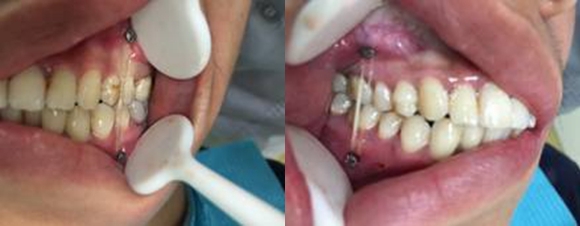

患者受傷以來,雙側后牙早接觸,前牙開牙合,開口受限,嚴重影響進食。患者因自身問題,拒絕上頜骨骨折切開復位堅強內固定術手術治療,一個多月后咬牙合關系紊亂加重,遂求治于我院口腔頜面外科,要求糾正咬牙合關系。

雙側后牙早接觸前牙開牙合

雙側牽引釘頜間牽引

牽引后咬合關系恢復良好